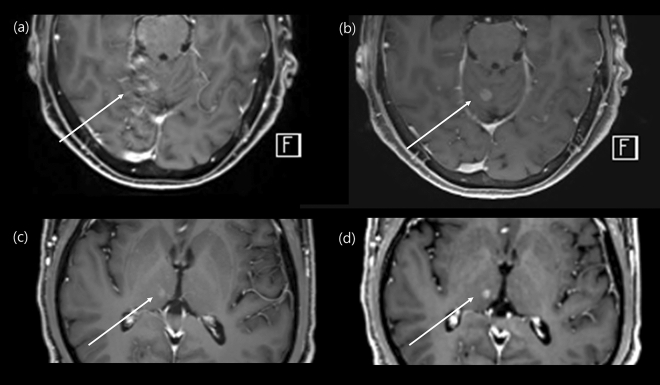

In this study, we demonstrated similar diagnostic accuracy of contrast-enhanced CS-VIBE and conventional post-contrast MPRAGE for the evaluation of intracranial metastasis. Using CS-VIBE, we could acquire a high resolution intracranial post-contrast image covering the whole brain in less than 3 min, which is less than half of the scan time of conventional MPRAGE. In addition, CS-VIBE exhibited better performance in terms of the enhancement degree and CNRlesion/parenchyma. Experienced radiologists rated CS-VIBE as providing a better overall image quality with less motion artifact; however, there was no significant difference in the preference between CS-VIBE and conventional post-contrast MPRAGE (Fig. 4). These findings support the broader application of a fast scan protocol using CS-VIBE sequences in the evaluation of patients with possible intracranial metastasis.

Figure 4.

Comparison of an enhancing intracranial lesion on conventional MPRAGE and CS-VIBE. A 67-year-old female and a 59-year-old male with intracranial metastasis from lung cancer in the right cerebellum (a, b) and right thalamus (c, d). Conventional MPRAGE (a, c) showed an irregular and indistinct enhancement whereas CS-VIBE (b, d) showed a discrete, nodular enhancement, which indicated metastasis.